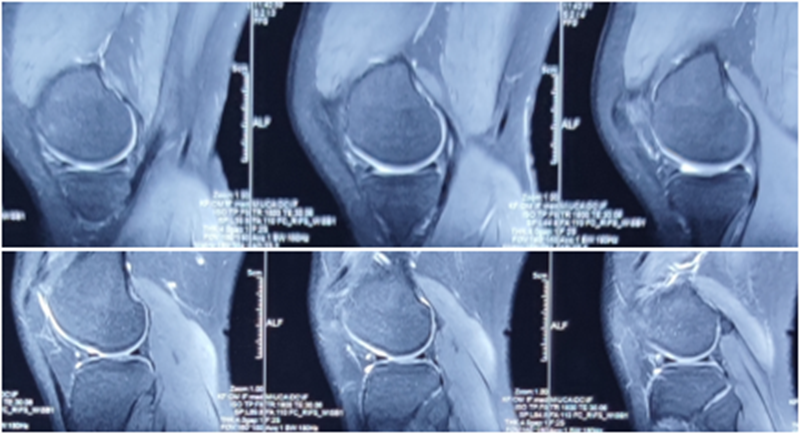

典型病例,张X,男,18岁,因扭伤致左膝关节疼痛伴活动受限1月余入院。

诊断:1.左膝前交叉韧带损伤;2.左膝外侧半月板损伤合并囊肿。

手术方案:左膝关节镜下清理、滑膜切除、外侧半月板部分切除成形、前交叉韧带重建术。

术前X线

术前MRI

术后MRI